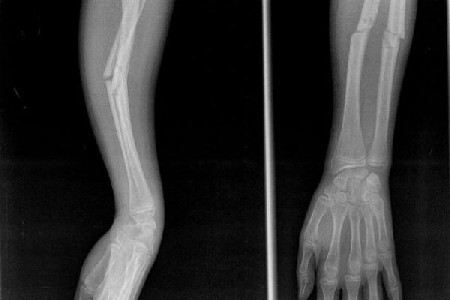

Echipa DelcMed este dedicată să ofere îngrijire medicală de calitate, punând la dispoziție soluții inovative și personalizate pentru fiecare pacient. Cabinetul nostru oferă servicii complete de ortopedie și traumatologie, inclusiv consultații specializate, infiltratii cu medicamente, reducerea fracturilor și luxațiilor, precum și mici intervenții chirurgicale pentru afecțiuni diverse. De asemenea, punem la dispoziție servicii de fizioterapie și kinetoterapie, cu tratamente personalizate pentru recuperarea post-operatorie, post-traumatică și pentru afecțiuni ortopedice și reumatologice. Beneficiați de tehnici moderne de tratament, precum PRP, infiltratii intraarticulare și periligamentare, alături de terapii cu laser, ultrasunet și electroforeză, pentru o recuperare rapidă și eficientă. Echipa noastră de specialiști vă oferă o gamă variată de proceduri, inclusiv pansamente aseptice, corecția unghiilor încarnate, drenarea hematomelor și tratamente pentru diverse afecțiuni dermatologice și neurologice.

Ai suferit o lovitură sau o fractură, ai dureri de articulații și oase? Nu aștepta - traumatologul te ajută să te vindeci corect!